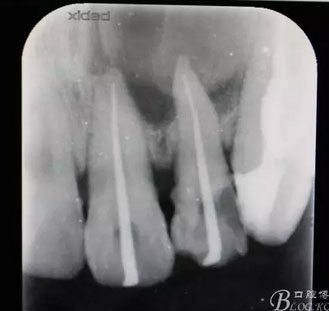

圖1.術(shù)前患者的x光根尖片檢查影像:22根尖完全位于囊腔內(nèi),牙槽骨吸收至嵴頂約5mm。22松動(dòng)Ⅰ度。